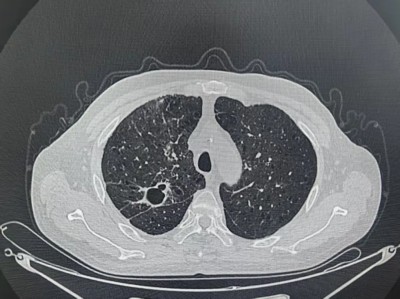

张大叔第三疗程治疗前后对比

治疗第一个疗程后

治疗第三个疗程后

3月下旬,顺利完成第3疗程治疗。复查结果令人振奋:肿瘤显著缩小,侵犯右主支气管的病灶大幅退缩,生活质量明显提升。